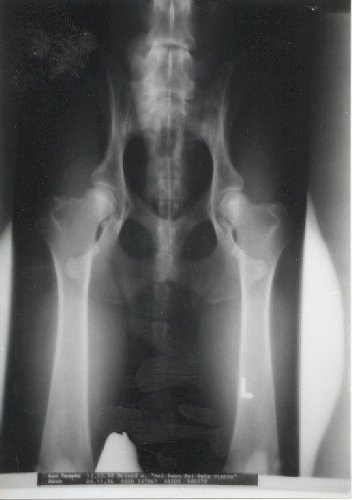

HD freies Gelenk